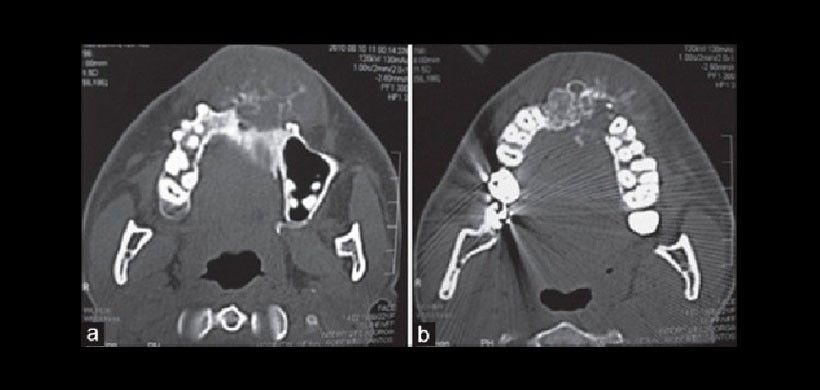

En los exámenes de imagen, como radiografías y tomografías computarizadas, el osteosarcoma se ha mostrado como una masa radiopaca o mixta, homogénea y central, multilocular y con límites mal definidos. Puede haber destrucción del hueso cortical e implicación de tejidos blandos adyacentes.

Figura 3: (A y b) La TC axial del maxilar mostró una lesión expansiva de carácter infiltrativo, con márgenes mal definidos, presentando un patrón variado de neoformación ósea causando la destrucción del hueso cortical.